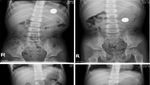

Seorang pria 50 tahun memiliki barbel sebesar 2 kg yang tersangkut dalam anusnya. Kasus ini sempat viral lantaran dinarasikan di Indonesia.

Faktanya, kasus ini terjadi di Pennsylvania, Amerika Serikat. Pria tersebut menjalani prosedur ekstraksi untuk mengeluarkan benda asing, beruntung tidak ada komplikasi hingga beberapa jam pasca tindakan yang bersangkutan diperbolehkan pulang. (Foto: Jurnal Cureus)